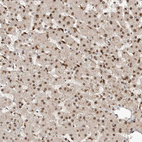

Immunohistochemical staining of human Testis shows moderate nuclear positivity in cells in seminiferous ducts.